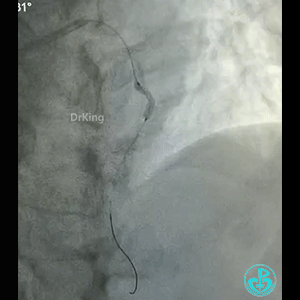

导丝怎么扩真怪!急性心梗前降支导丝通过顺利,球囊扩张后导丝移位很多!不在原来的血管腔!_https://www.jmylbn.com_新闻资讯_第2张

怎么解释导丝和血管的关系?

BMW导丝,预扩前导丝是弯曲的,预扩时球囊也是弯曲的,预扩后导丝拉直,血管的弯曲还在。